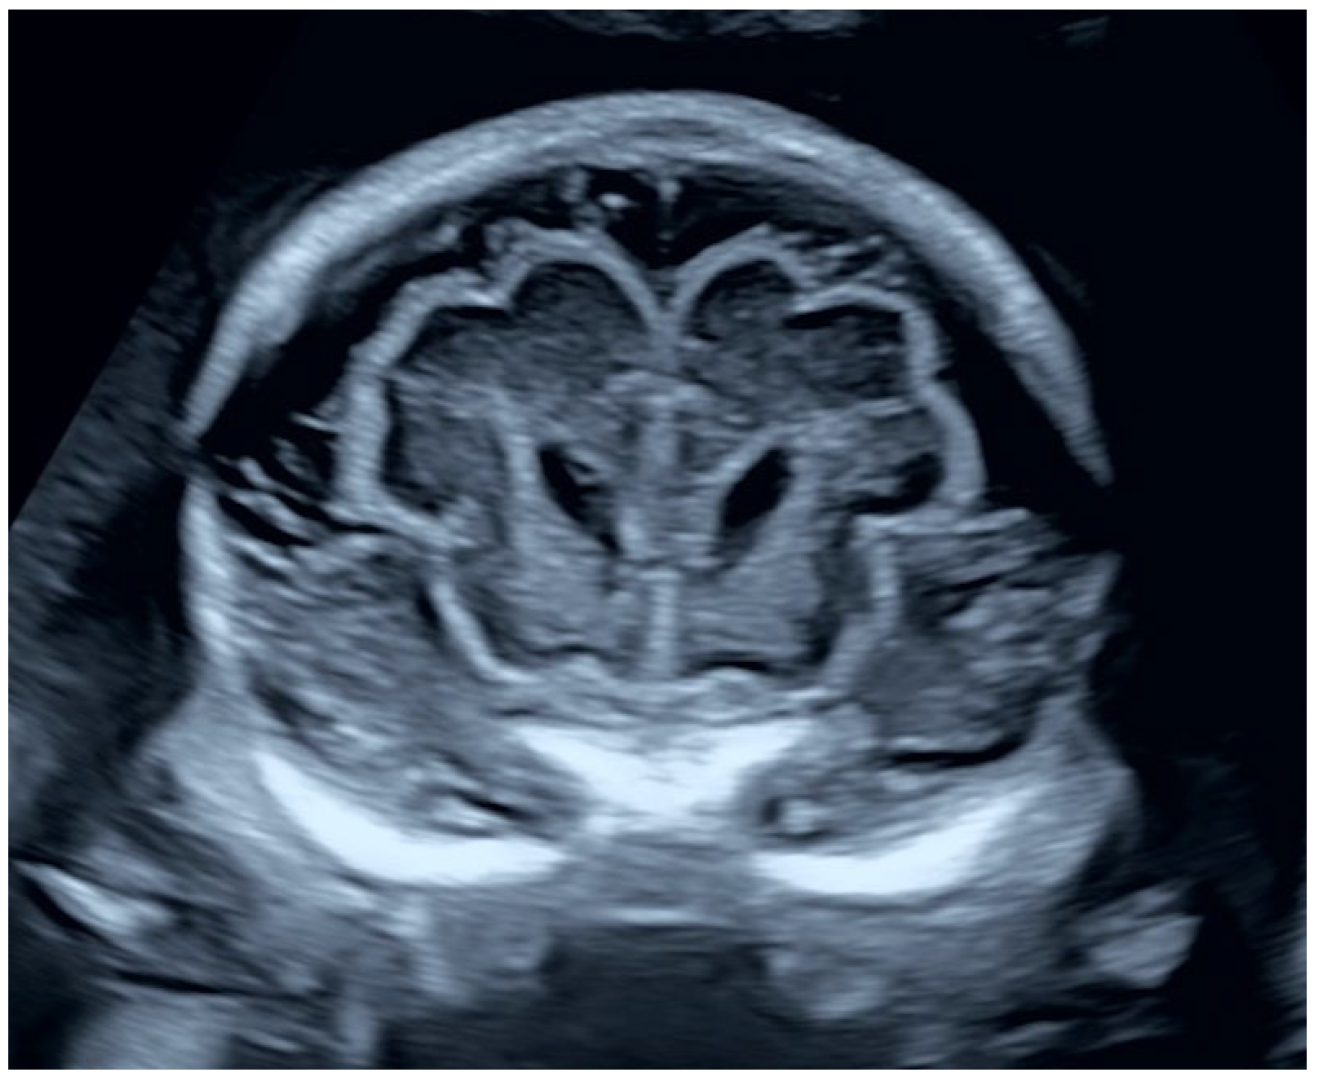

2.1.2. Ultrasound Findings

2.2.2. Ultrasound Findings